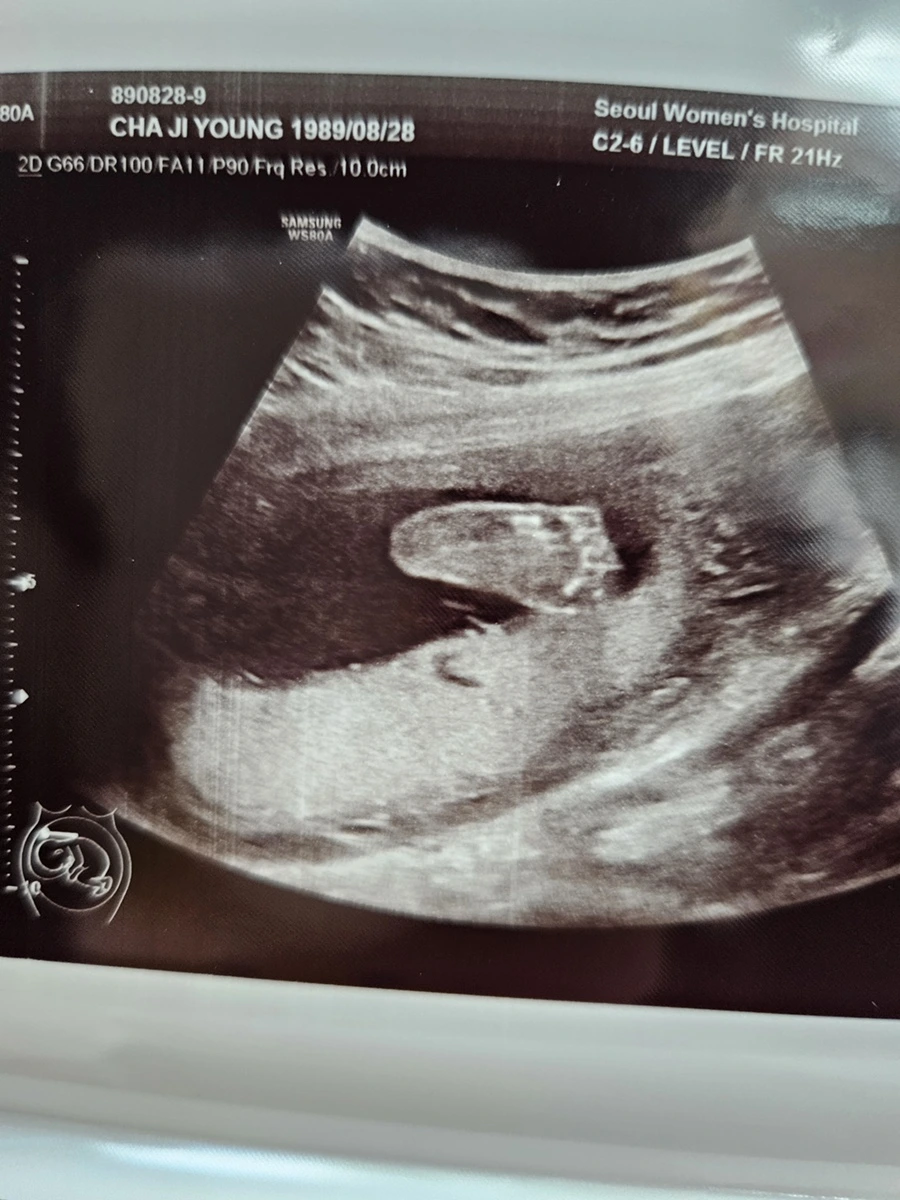

이전에 짧게 짧게 머리둘레, 배 등 간단히 보던 초음파와 다르게 영상 속에서 아기가 활발하게 움직이는 모습과 얼굴까지 포착되니 남편과 나는 정말 신기했다. 뱃속에서 아기가 다섯개의 손가락과 다섯개의 발가락 뿐만 아니라 포즈를 취하면서 놀고 있는 모습을 본다는 것이 정말 생경한 경험이었다.

아기의 발바닥과 peace를 날려주고 있는 아기의 손가락